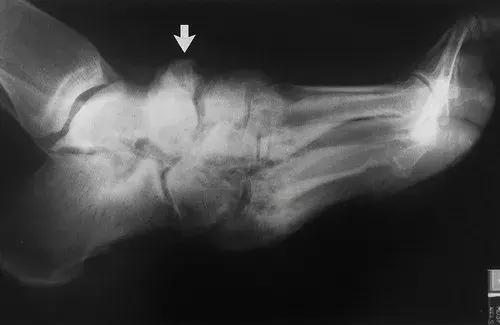

图17:42岁男性糖尿病人,踝关节和后足的神经性骨关节病。侧位X线片显示胫骨远端破坏吸收,并且具有类似于手术截肢的尖锐边缘。 距骨圆顶被吸收。 存在硬化,并且不再能够识别距下关节(箭头)。